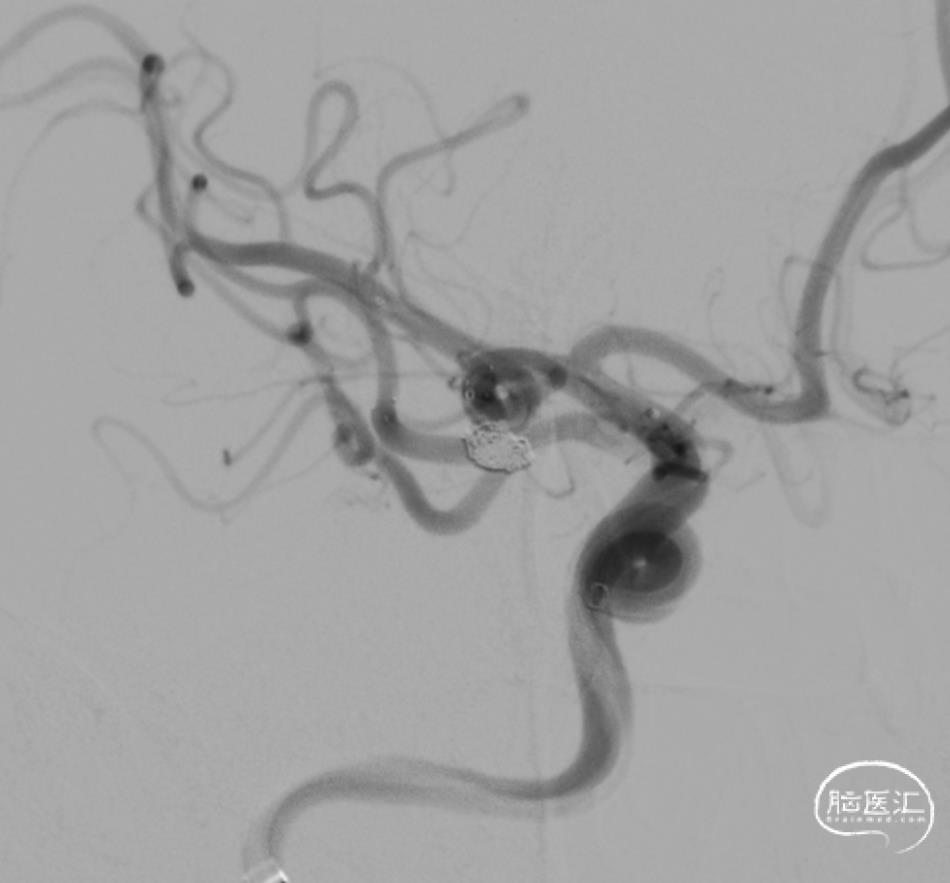

术前影像资料:

弓上造影:II型弓

超选右侧ICA正位及侧位造影

3D-RA成像

动脉瘤位于M1分叉处,三分支。